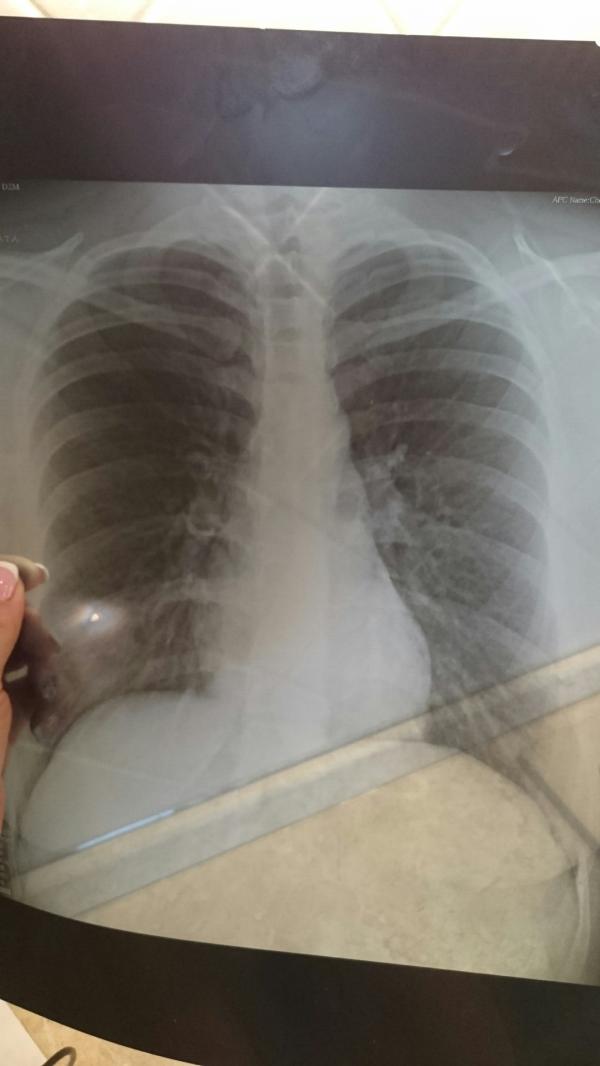

Девочки добрый день, скажите есть среди вас врачи которые могли бы посмотреть снимок легких. И сказать все хорошо или есть бронхит.